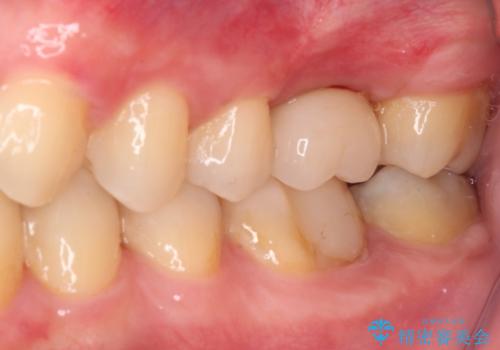

- 前歯のクロスバイトと、大学生のころから放置している虫歯を気にして来院された患者様です。

マウスピースでの矯正治療を希望されていましたが、前歯のクロスバイトは不十分な仕上がりや歯髄壊死などのリスクが高くなるため、術前にワイヤーで大まかに整えてからインビザラインにて矯正治療を行うこととしました。

奥歯の虫歯は抜歯が必要であったので、矯正治療前に抜歯をし、矯正治療と並行してインプラントによる補綴治療を行うこととしました。

当院の特徴は、矯正治療とインプラント補綴治療の担当医が同じ歯科医師であるため、両方の治療を並行して行うことができます。